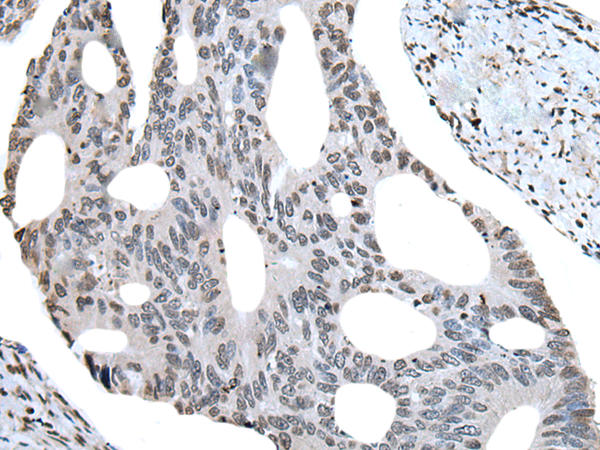

IHC positive control: |

Human colorectal cancer |

IHC Recommend dilution: |

20-100 |